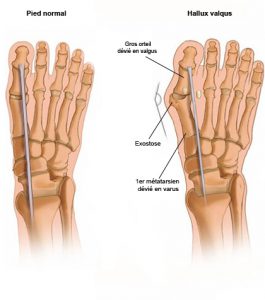

Hallux Valgus Clinique du pied